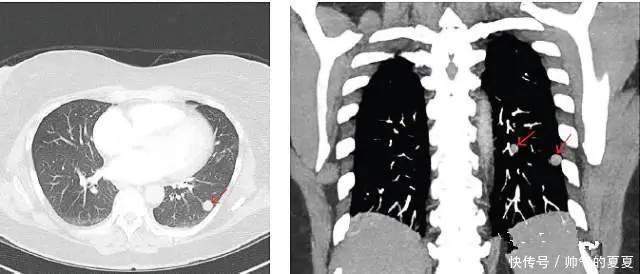

图3 ?实性结节第三种,混杂型磨玻璃结节(mixed Gross glass nodule,mGGN)这种结节处在前两者的“中间”,在CT图像上表现为磨玻璃和实性结节的混合,磨玻璃阴影里还带有,实性成分。

文章插图

图4 ?混杂磨玻璃结节3种结节,既可能是良性的,也可能是恶性的。良性的有球形肺炎、结核球、错构瘤良性、纤维增生。恶性的结节往往有一些特殊表现会写在你的CT报告单上,如“毛刺征”“分叶征”“胸膜牵拉征”“微血管征”“棘突征等”。治病有一大黄金准则是“早发现、早诊断、早治疗”,特别对于癌症!那如何更准确的进行诊断?这也是大家关心的问题。案例:“良、恶”难辨,要做“肺癌自身抗体检测”51岁的李某,男,2020年体检发现肺部结节,胸部CT:右下肺磨玻璃结节,约7mm大小,其内低密度影。遂到我院就诊,首次CT及追踪3月后CT所报结果均不能区分结节是良性还是恶性。单独做CT难以评估结节性质,患者本身也较为焦虑,遂建议其验血做“肺癌自身抗体检测”,结果显示:SOX2阳性;GBU4-5阳性。两方联合诊断高度怀疑肺部肿瘤,患者很快便选择进行手术治疗。手术切除后病检结果显示:(右下肺背段)肺微浸润性肺癌。什么是肺癌自身抗体检测?“肺癌自身抗体检测”是核医学科近年引进的一个新兴超早期肺部肿瘤筛查项目,只需要抽一管血,便可结合CT有效地进行肺癌初诊。人体在各种致癌因素影响下,我们的免疫系统识别这些肿瘤细胞,做出应答,并且针对这些肿瘤细胞上的特异性抗原,而产生相应的抗体,这些抗体就称为“自身抗体”。